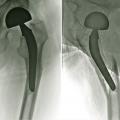

En cas de fracture cervicale vraie Garden III ou IV, le risque de nécrose est important, et il est préférable de s’orienter vers un remplacement prothétique (fig. 14). Il peut s’agir d’une prothèse céphalique où la prothèse remplace uniquement la tête fémorale. Il peut s’agir d’une prothèse intermédiaire qui remplace la tête fémorale mais avec un système de double glissement qui améliore la stabilité de l’implant et diminue les risques d’usure de l’acetabulum. Il peut s’agir d’une prothèse totale de hanche. L’utilisation ou non du ciment pour la fixation de la prothèse ne fait pas consensus dans la littérature, chaque méthode ayant ses avantages et ses inconvénients. Toutefois, chez les patients jeunes, en général de moins de 50 ans, malgré les risques de nécrose, l'ostéosynthèse est conseillée, même dans les fractures Garden III et IV.